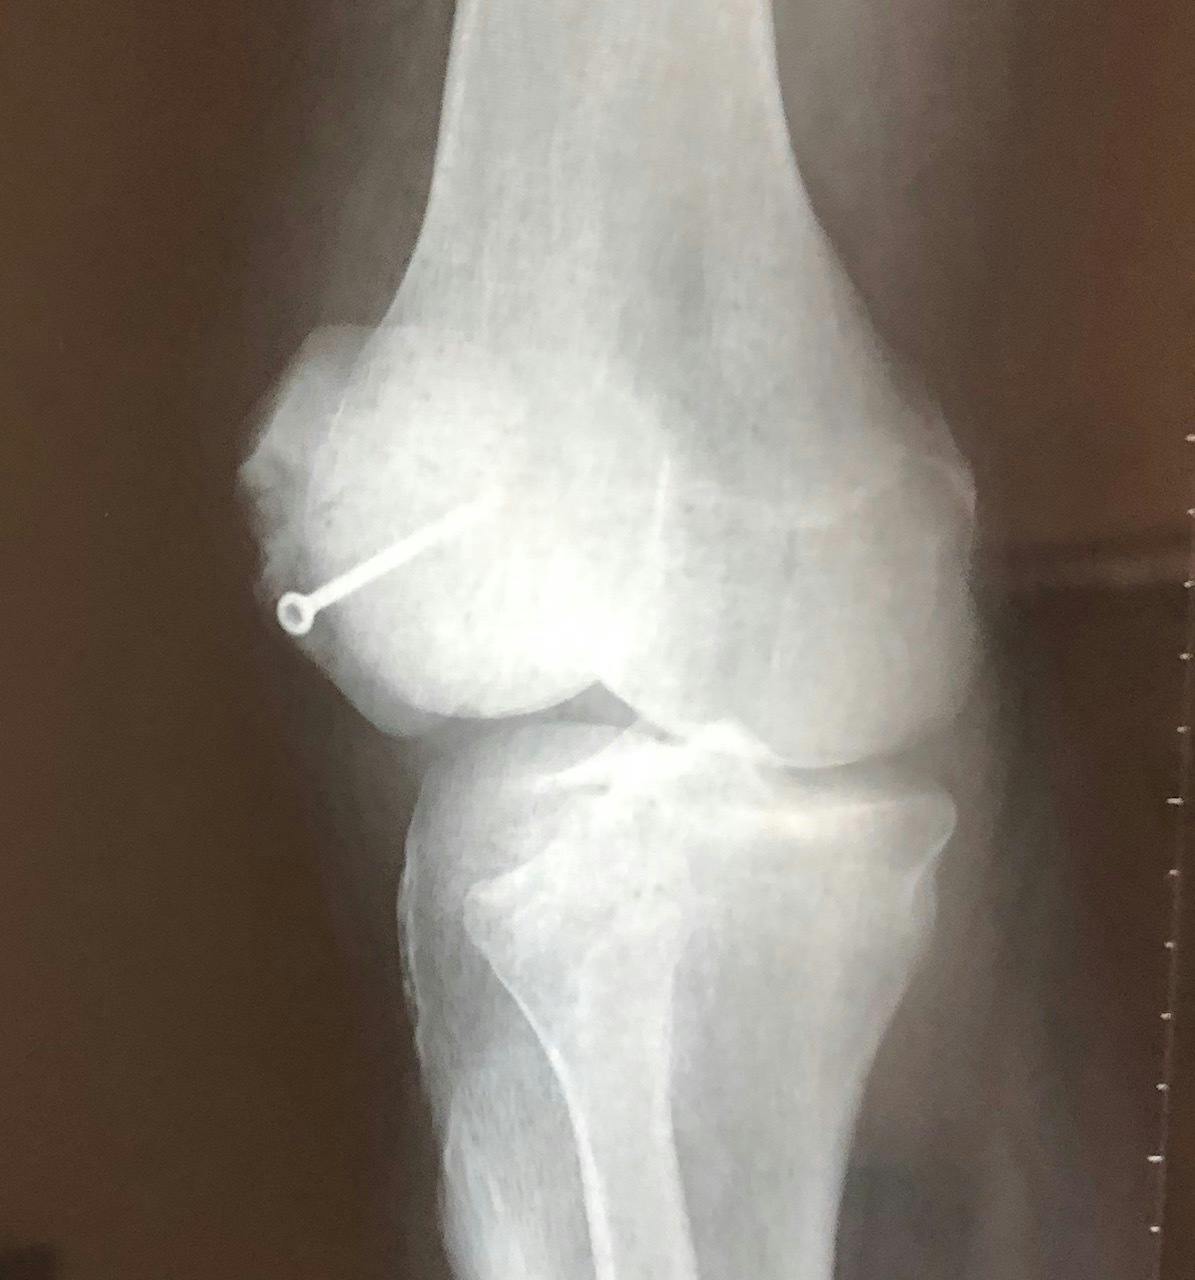

写真でご覧のとおり、見るからに元気ではあるのですが、実はぼくの身体は大動脈が人工血管になり、右足の大腿骨と膝は数本のボルトで繋がれています。

(以下、レントゲンや縫合後のお見苦しい画像がありますがご容赦ください)。